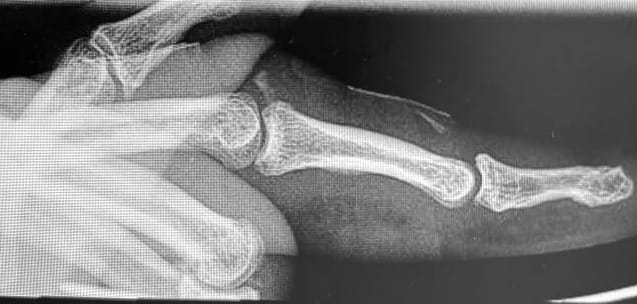

X-rays demonstrated a volar dislocation of the left ring finger PIP joint, with two small osseous fragments visible within the dorsal joint recess. The dislocation was easily reduced under a local anaesthetic ring block.

Post-reduction, the joint was clinically unstable and would re-dislocate with flexion of the PIP joint. The finger was immobilised in extension using a splint, and the patient was referred to hand therapy, with the instability noted in the referral. The report of the post reduction film suggested that there was a minor avulsion from the head of the proximal phalanx.

One week later, the patient re-presented with another volar dislocation of the same PIP joint. The hand therapist had replaced the original Zimmer splint with a thermoplastic splint. The patient reported striking his hand against a wall after waking suddenly. The dislocation was again reduced under ring block. Following this second reduction, the finger demonstrated a mild Boutonnière deformity. This time the radiology report suggested that the avulsion fragment was from the base of the middle phalanx.